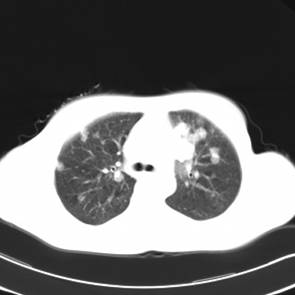

影像学检查:

CT左侧乳腺癌保乳治疗术后,双肺发转移瘤;

右肺中叶炎症;

两个月后患者到医院复查CT发现,双肺发转移瘤明显实现了瘤体萎缩。